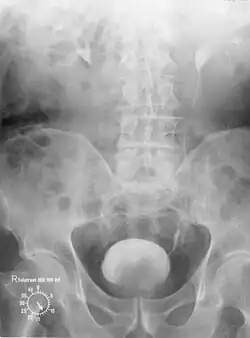

Pyelogramm

Wilhelm Conrad Röntgen entdeckte 1895 die nach ihm benannten Röntgenstrahlen. Damit begann die Entwicklung der Radiologie. Was die Urologie betrifft, wurde 1906 erstmals die von Friedrich Voelcker und Alexander von Lichtenberg entwickelte „retrograde Pyelographie“ vorgestellt, wobei das Nierenbeckenkelchsystem und die Harnleiter mit einer Kollargol-Lösung dargestellt wurden. Es kam dabei jedoch zu schwersten Nebenwirkungen.[53] 1927 wurden von Maurice Chevassu Harnleiter und Nierenbecken mit Kontrastmittel, das im Rahmen einer Blasenspiegelung direkt in die Harnleitermündung eingebracht wird, dargestellt.[54] 1929 führte von Lichtenberg die Pyelographie, d. h. die Darstellung der ableitenden Harnwege über in die Vene eingebrachtes Kontrastmittel, wieder in die Diagnostik ein. Am 28. September 1929 wurden auf dem 9. Deutschen Urologen-Kongress in München von Alexander von Lichtenberg und Moses Swick[55][56] erstmals die Fachwelt überzeugende Urogramme (mittels des durch die Chemiker Arthur Binz und Curt Räth entdeckten Uroselectan)[57] und damit erstmals brauchbare Röntgenbilder der Niere demonstriert.[58][59] Damit waren neue Wege der Diagnostik eröffnet.[60] Die Röntgenfotografie wurde bei einer Nierensteinoperation erstmals von dem Nürnberger Urologen Eduard Pflaumer durchgeführt.[61] Die 1973 eingeführte axiale Computertomographie ermöglichte auch in der Urologie weitere Verbesserungen.